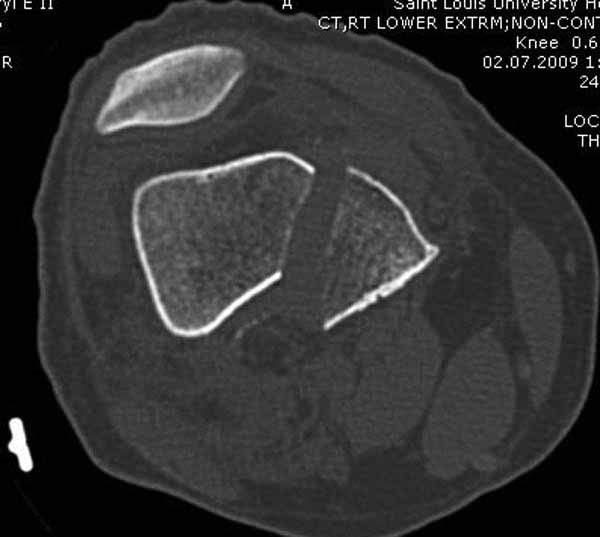

Представленный снимок не дает полную информацию. Там вроде простой перелом, но на самом деле, кроме смещенного (латерального, возможно медиального?) мыщелка на второй проекции имеется медиальный короткий дистальный фрагмент в флексии. Надо было сделать прямой снимок с захватом малоберцовой, который ориентировал бы стороны. Без КТ обычный снимок в дистракции поможет разобраться в топографии фрагментов.

Во время фиксации надо соблюдать осторожность, особенно с коротким фрагментом на другой стороне. Обычно на прямой проекции трудно заметить флексионную деформацию мыщелка и упускается адекватная фиксация. Без пластины винты не смогут удержать, и мыщелок на второй стороне может сместиться. Для фиксации надо развернуть мыщелок и удержать винтами. Качество межмыщелковой репозиции надо проконтролировать артротомией. Из всех доступов только передне-латеральный доступ (Swashbuckler) даст обзор для ревизии качества фиксации, который в будущем может быть использован для артропластики.

Кстати, из вашего снимка, если отмечены вашим рентгенологом правильно, тогда получается снимок левого колена, и, соответственно, длинный переходящий в диафиз мыщелковый фрагмент находится медиально. Если так, тогда меняется сценарий фиксации!!!

И не обратите, коллега, пока не сделаете четкие анфасные снимки (лучше с дистракцией) где будет четко визуализироваться малоберцовая кость. Думается, что и КТ здесь будет уместно, дабы не пропустить возможное флексионное повреждение (перелом Hoffa).

А теперь по поводу лечения перелома. Среди всех чрез/меж-мыщелковых переломов в 38% сопровождются переломом в корональной плоскости, т.е перелом Hoffa. Nork et al, J Orthop Trauma, 87:564, 2005.